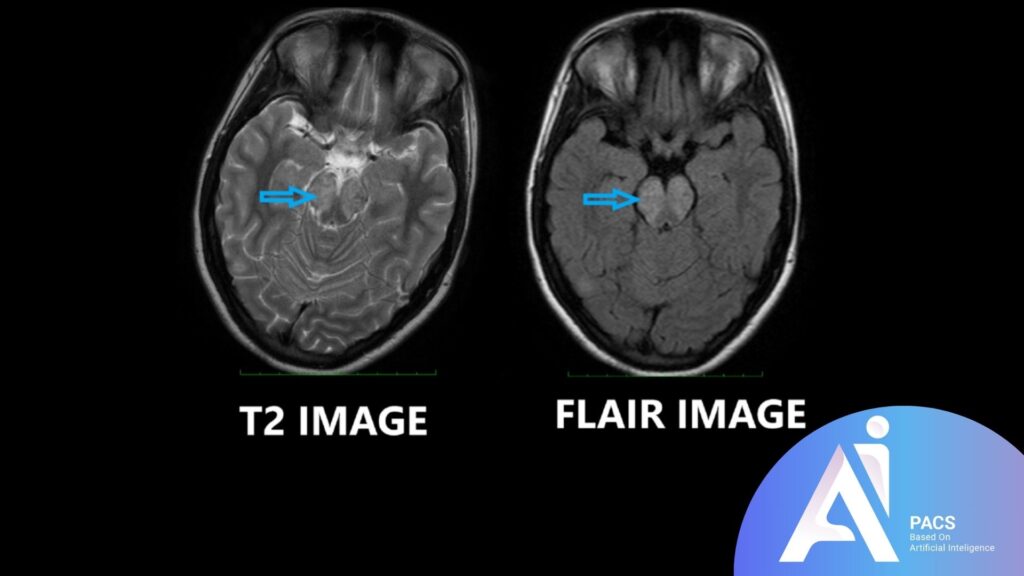

Comparison to other MRI sequences for context

Compared to standard T1 and T2 MRI sequences, FLAIR provides a unique advantage in brain imaging by isolating abnormalities near or within fluid-filled spaces. While T2-weighted imaging also highlights areas of high water content, the bright CSF can obscure details, especially near the brain’s ventricles. In contrast, FLAIR’s fluid suppression reveals subtle brain lesions, making it a crucial tool for diagnosing conditions like multiple sclerosis, stroke, and infections that might be harder to detect with other sequences.

FLAIR MRI is particularly effective at bringing certain brain abnormalities into sharper focus. By suppressing the bright signals of cerebrospinal fluid (CSF), FLAIR helps radiologists detect subtle changes in brain tissue that might be missed on standard MRI sequences. Here are some of the common abnormalities FLAIR can reveal: